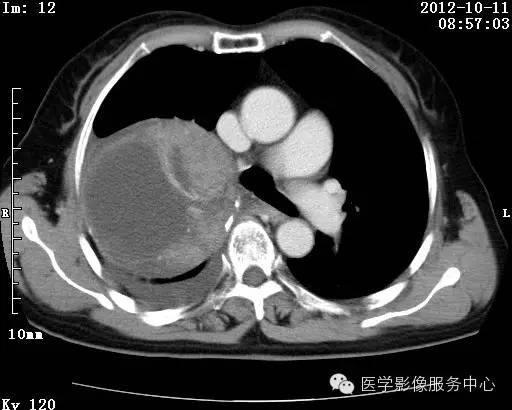

【病例】右肺巨大错构瘤1例CT影像表现

病史:女 65岁咳嗽咳痰 右肺巨大肿块就诊。

错构瘤的发病年龄多数在40岁以上,男性多于女性。 绝大多数错构瘤(约80%以上)生长在肺的周边部,紧贴于肺的脏层胸膜之下,有时突出于肺表面。其特征钙化为爆米花样钙化,内有脂肪软骨成分等等。最常见的部位是胸膜下肺实质内,其次为主支气管或肺叶、肺段支气管内。

理论上肺错构瘤为良性肿瘤,其结节形态、边界、与胸膜关系、与肺门关系、淋巴结肿大及与血管关系均应符合良性肿瘤的特点。

瘤内出现“爆米花样钙化”是诊断的主要指标之一。早期的点状、斑片状及结节状钙化 随时间增加钙化数量及范围会增加,最终可能演变 为爆米花样钙化;

另一项主要指标是瘤测得脂肪成分是诊断错构瘤。